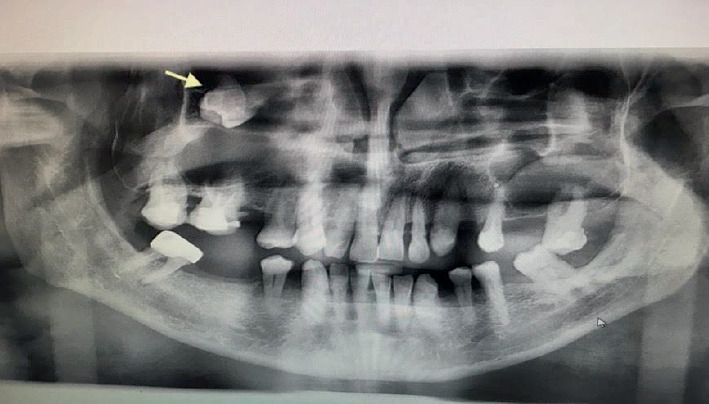

恒磨牙异位萌出是一种罕见的发育异常,其特征是牙位异常,可导致严重的并发症。在罕见的情况下,异位磨牙可能与含牙囊肿有关,特别是在上颌窦内,对诊断和治疗提出了挑战。本文报告一位58岁男性病患,表现为慢性右上颌鼻窦炎、间歇性面部疼痛及脓性鼻及口腔分泌物。放射学评估,包括锥束计算机断层扫描(CBCT),显示一个完全不透明的右上颌窦包含一个异位上颌磨牙。此外,发现一个与含牙囊肿一致的大囊性病变,占据整个窦腔。手术在全麻下采用Caldwell-Luc入路。这包括在上颌前壁制造一个骨窗,以方便切除异位牙和相关的囊性病变。组织病理学检查证实有牙性囊肿,表现为慢性炎症浸润和纤维化。上颌窦的异位磨牙通常无症状,但可表现为反复的鼻窦炎、疼痛和口窦沟通。存在一个大的含牙囊肿增加并发症的风险,并可能模糊放射学解释由于窦混浊。该病例强调了综合影像学检查和早期手术干预的必要性,以防止长期并发症。意识到这种罕见的情况可以帮助临床医生及时诊断和适当的管理,最终保留鼻窦功能,并尽量减少进一步的问题。

Ectopic eruption of permanent molars is an uncommon developmental anomaly characterized by abnormal tooth positioning, which can lead to significant complications. In rare instances, ectopic molars may be associated with dentigerous cysts, particularly within the maxillary sinus, posing challenges for diagnosis and management. This report discusses a rare case of a 58-year-old male who presented with chronic right maxillary sinusitis, intermittent facial pain, and purulent nasal and oral discharge. Radiological evaluation, including cone beam computed tomography (CBCT), revealed a completely opacified right maxillary sinus containing an ectopic maxillary molar. Additionally, a large cystic lesion consistent with a dentigerous cyst was found, occupying the entire sinus cavity. Surgical management was performed using the Caldwell-Luc approach under general anesthesia. This involved creating a bone window in the anterior maxillary wall to facilitate the removal of the ectopic tooth and the associated cystic lesion. Histopathological examination confirmed the presence of a dentigerous cyst exhibiting chronic inflammatory infiltration and fibrosis. Ectopic molars in the maxillary sinus are often asymptomatic but can present with recurrent sinusitis, pain, and oroantral communication. The existence of a large dentigerous cyst heightens the risk of complications and may obscure radiological interpretation due to sinus opacification. This case highlights the necessity of comprehensive imaging and early surgical intervention to prevent long-term complications. Awareness of such rare conditions can help clinicians in prompt diagnosis and appropriate management, ultimately preserving sinus function and minimizing further issues.